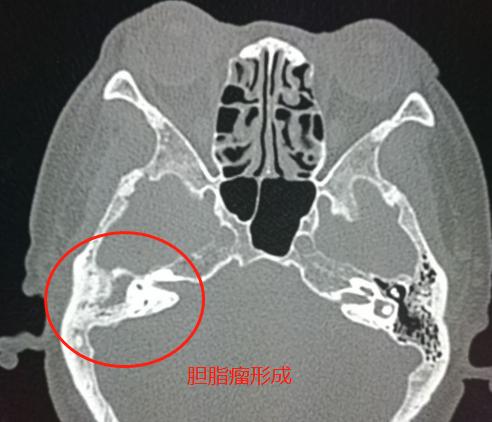

3.中耳炎继续进展,乳突周围骨质破坏,形成胆脂瘤(恶臭)——

局部骨质破坏,形成具有恶臭味的胆脂瘤

慢性中耳乳突炎多年,反复发作,发生了胆脂瘤,中耳结构破坏,听力明显下降。

到这个时候就只能手术治疗了。